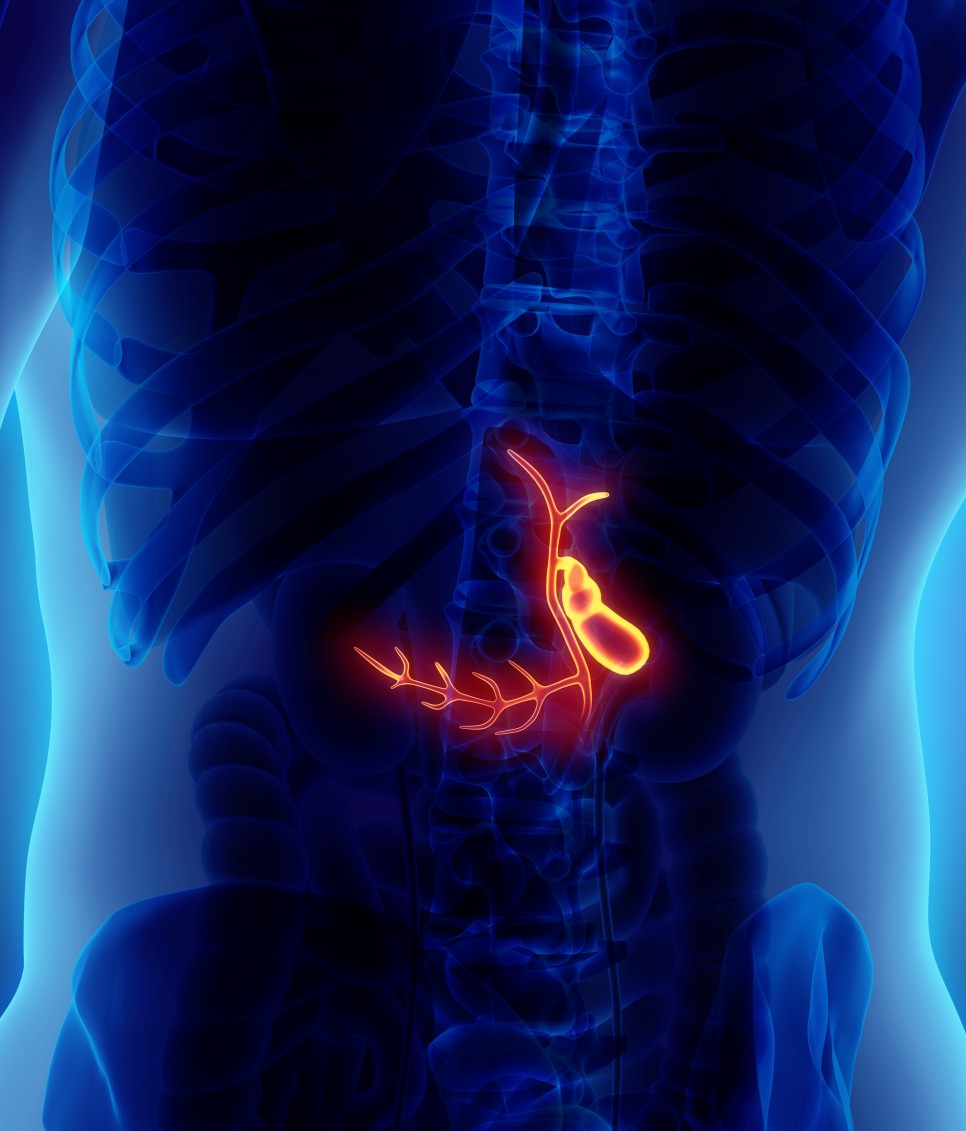

담낭은 순우리말로 담낭이라고 불리는 기관으로 담즙을 농축, 저장하는 기능을 하는 기관입니다. 어른 주먹의 약 절반 크기의 주머니 모양을 하고 있는데, 음식을 섭취할 경우 수축하면서 담즙을 십이지장으로 배출시켜 음식물 소화 등을 돕는 역할을 합니다. 이러한 역할을 하는 과정을 위해 담즙을 십이지장으로 배출하는 담관이 형성되어 있는데 담관의 끝은 췌관과 만나 십이지장으로 이어지는 구조를 가지고 있습니다. 따라서 이러한 췌장 또는 담관에 질환이 생긴 경우에는 담낭에도 마찬가지로 이상이 생길 수 있습니다.

담낭에 염증이 생기는 담낭염은 진행 정도와 원인에 따라 급성과 만성으로 구별할 수 있습니다. 대부분은 담석에 의해 발생하지만 담석이 담낭관 입구를 막거나 담석에 의해 만성적으로 담낭벽이 자극되는 경우 담낭 내에 균이 증식하거나 담낭벽에 세균감염이 유발되어 염증을 일으키게 되며 이로 인해 질환으로 발전할 수 있습니다.

따라서 담낭염은 가급적 조기에 진단해 빨리 치료를 받는 것이 바람직하다. 오랜 소화불량과 복부의 불쾌감이 담낭염의 주요 증상인데, 지속적으로 담낭에 염증반응이 발생하면 담낭의 기능이 감소하고 염증반응이 장기간 발생하면 담낭암으로도 이어질 수 있습니다.